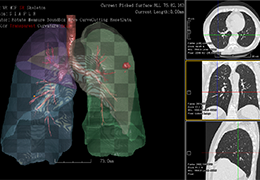

Segmentation

Segmentation of tissue (e.g., isolating the brain, differentiating gray and white matter) is performed using region-growing methods, filter operations as well as the application of 3D templates. Using the mouse it is very easy to explore a 3D volume with superimposed pseudocolor-coded statistical maps in a four-window representation showing a sagittal, coronal, transversal and oblique section. Based on a (segmented) 3D data set a three-dimensional reconstruction of the subjects' head and brain can be calculated and displayed from any specified viewpoint using volume or surface rendering.

Advanced segmentation tool means even higher quality segmentation of grey and white matter and boundaries.